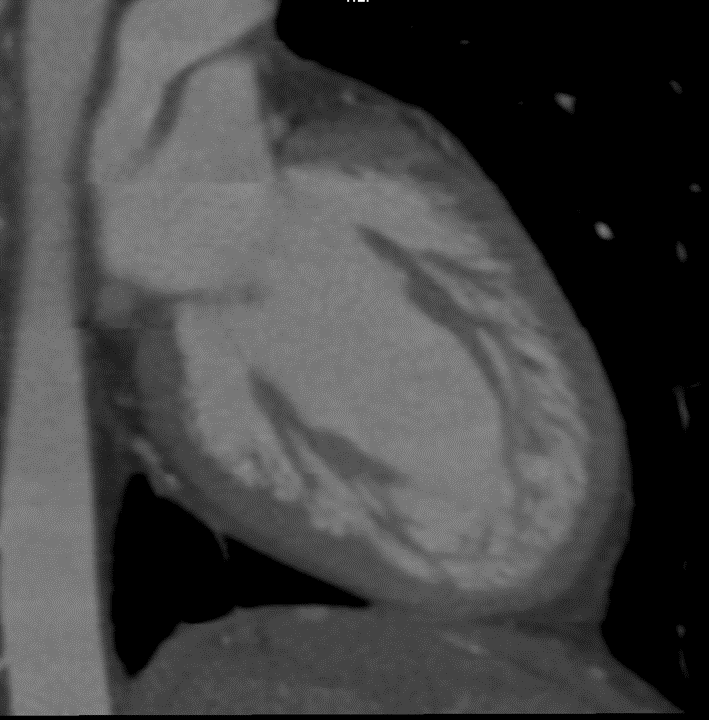

CT Scan

Example showing increased trabeculations along the wall of the left ventricle.